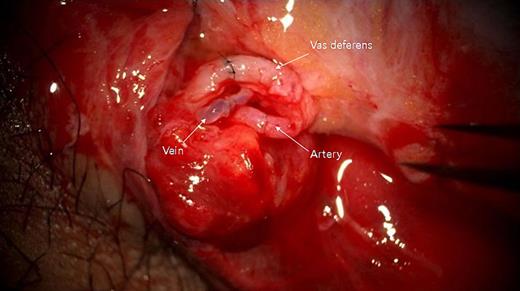

Cooperative surgery was performed by surgeons from the urology and plastic surgery departments. The patient was placed supine in a frog-leg position. The proximal gonadal artery in the spermatic cord was detected easily with pulsating bleeding and secured by clamping without causing vessel injury (Fig. 2). The vas deferens was also found near the gonadal artery with a resilient tactile sense. Thin lumens around the gonadal artery were identified as gonadal veins. The amputated testis was also checked, and the vas deferens was continued from the tail of the epididymis. The gonadal artery was located in the same direction as the vas deferens. The testis was fixed on the scrotal wall to prevent it from roaming freely. The gonadal artery was first connected using 11-0 nylon under an operating microscope (KINEVO 900, Zeiss; Fig. 3). After vein drainage was confirmed, gonadal vein anastomosis was performed with 11-0 nylon (Fig. 3). Lastly, two-layer vasovasostomy was carried out with 8-0 nylon (Fig. 3). After the end-to-end anastomosis of the artery, vein, and vas deferens, the viability of the testis could be confirmed in terms of vascularity on gross and indocyanine green fluorescence perfusion (Fig. 4). The cremasteric muscle of the spermatic cord was reinforced to reduce tension in the anastomosis sites, and orchiopexy was performed to prevent testicular torsion. The other testis was replanted in the same maneuver (right testis: artery 1ea, vein 1ea; left testis: artery 1ea, vein 2ea). The ischemic time of each testis was 7 h (right) and 8.5 h (left). Each testis was raised on a high scrotal area and fixed with the approximated dartos fascia because of the large skin defect of the scrotum (Fig. 5). Lastly, the amputated scrotal wall after defatting was used to cover the whole defect.

Self-amputation is characterized by a clearly cut plane without any hesitation. In this case, the amputated testis had a simple and clear-cut plane. The right testis had long remnant vessels and vas deferens, which could help detect the anatomical parts and anastomose easily. Although the left testis had extremely short vessels and vas, these parts could be connected via microscopy, and the testis was recovered. Testicular vascular supplies are composed of the gonadal (testicular) artery from the aorta, the vasal artery from the internal iliac artery, and the cremasteric artery from the inferior epigastric artery [6]. Among them, the gonadal artery was the main supply source [7]. One gonadal artery was anastomosed, and the testis survived with normal testosterone levels.